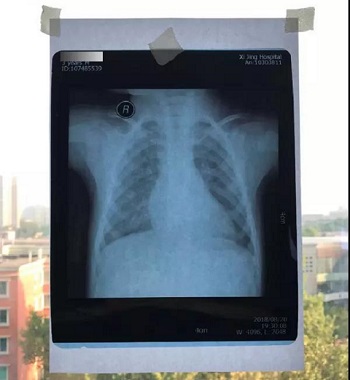

片子反光,背景无透射光

把片子直接贴在窗户玻璃上拍,窗户外面的风景透过片子拍入了照片上,图片的下半部分,可以隐约看到窗户外面的建筑,影响医生阅片,不能获取有价值的磁共振信息。